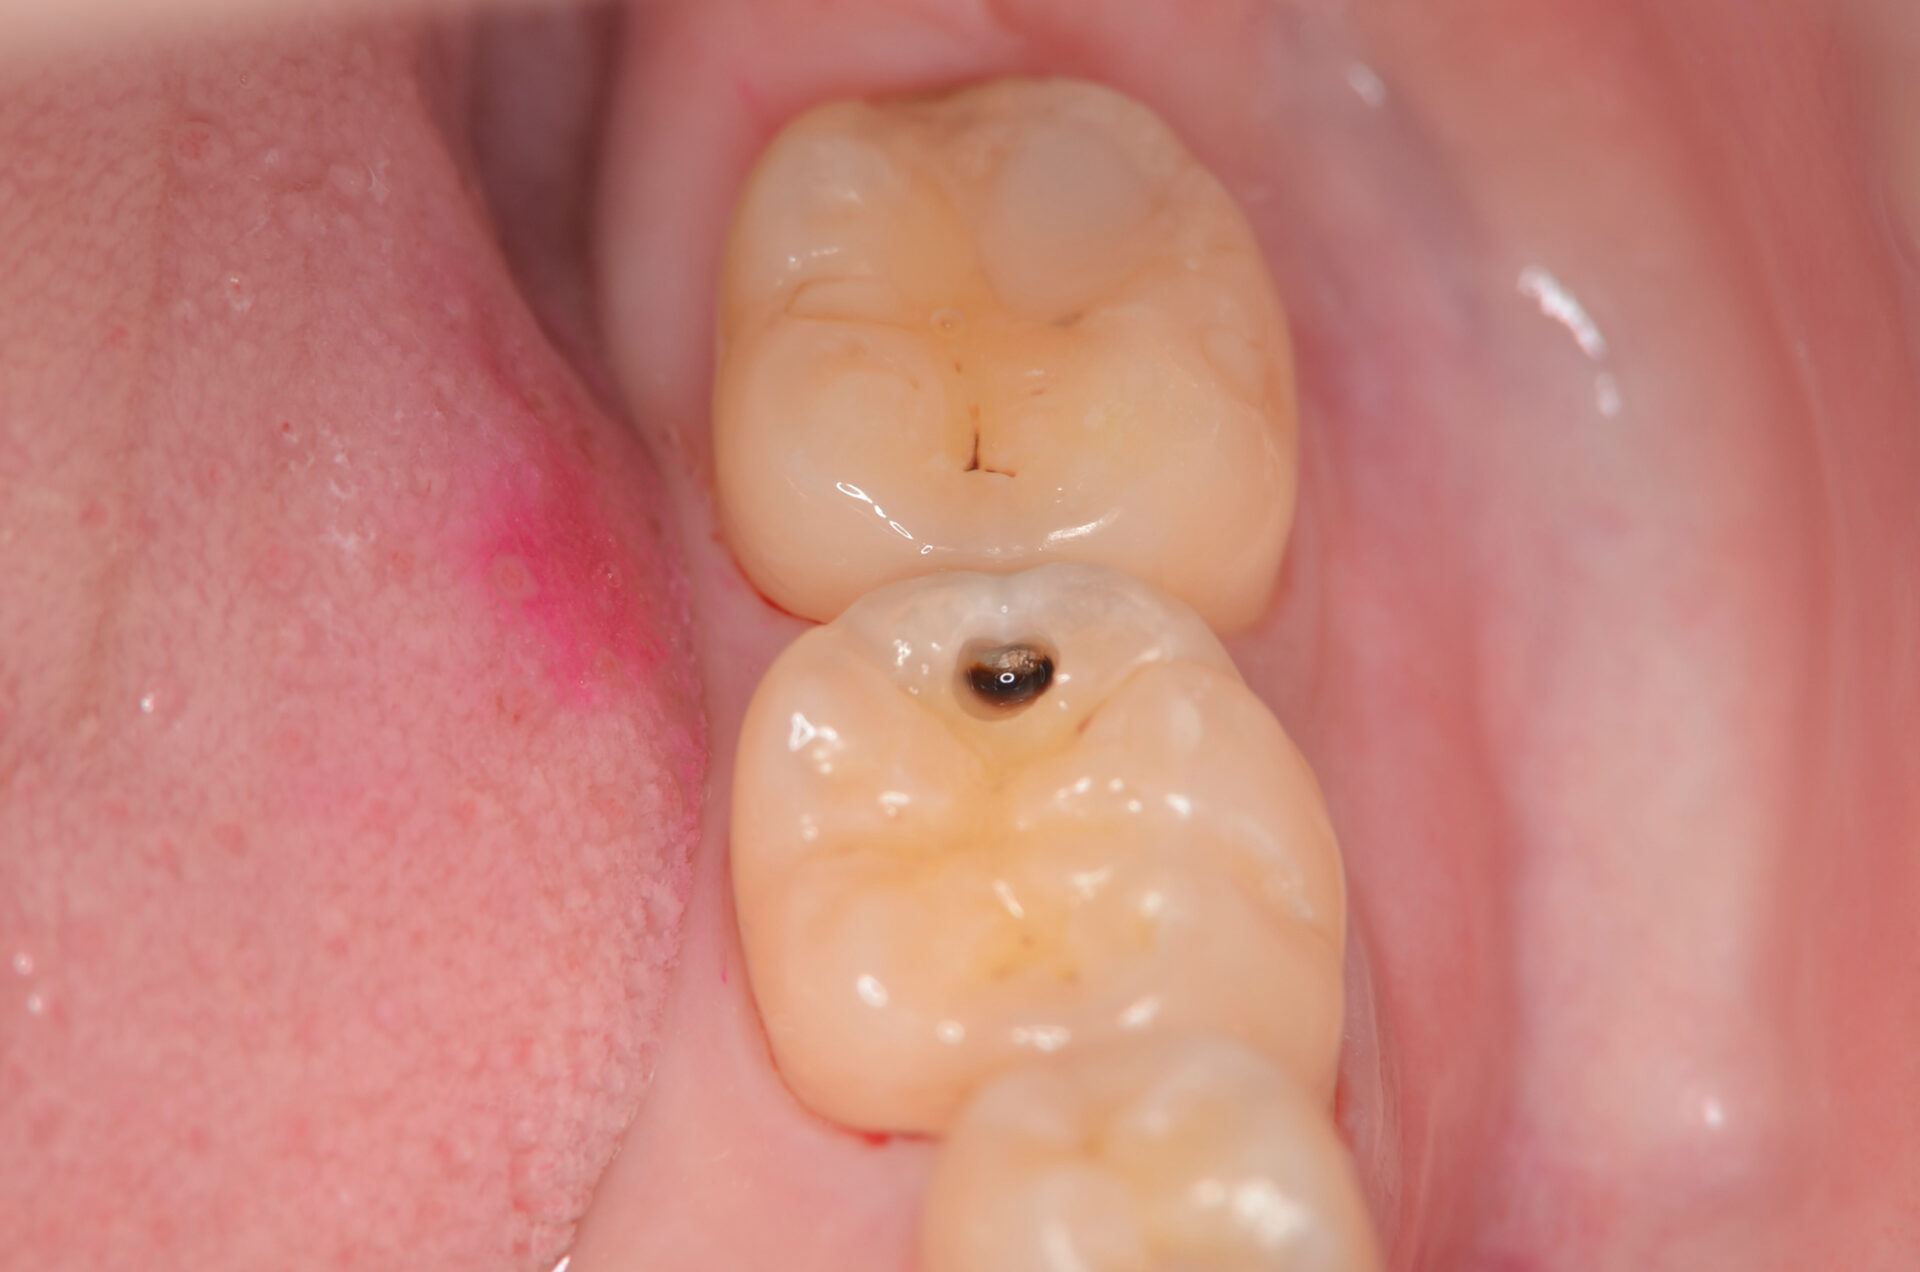

露髄

1週間後に治療の続きをします。 完全に虫歯を取り切ると露髄しました。 -

MTAセメント

露髄面にMTAセメントを充填しました。 -

スーパーボンド

スーパーボンドでMTAセメントを覆います。 -

ダイレクトボンディング

天然歯の自然な形態を模倣してレジンを充填しました。 -